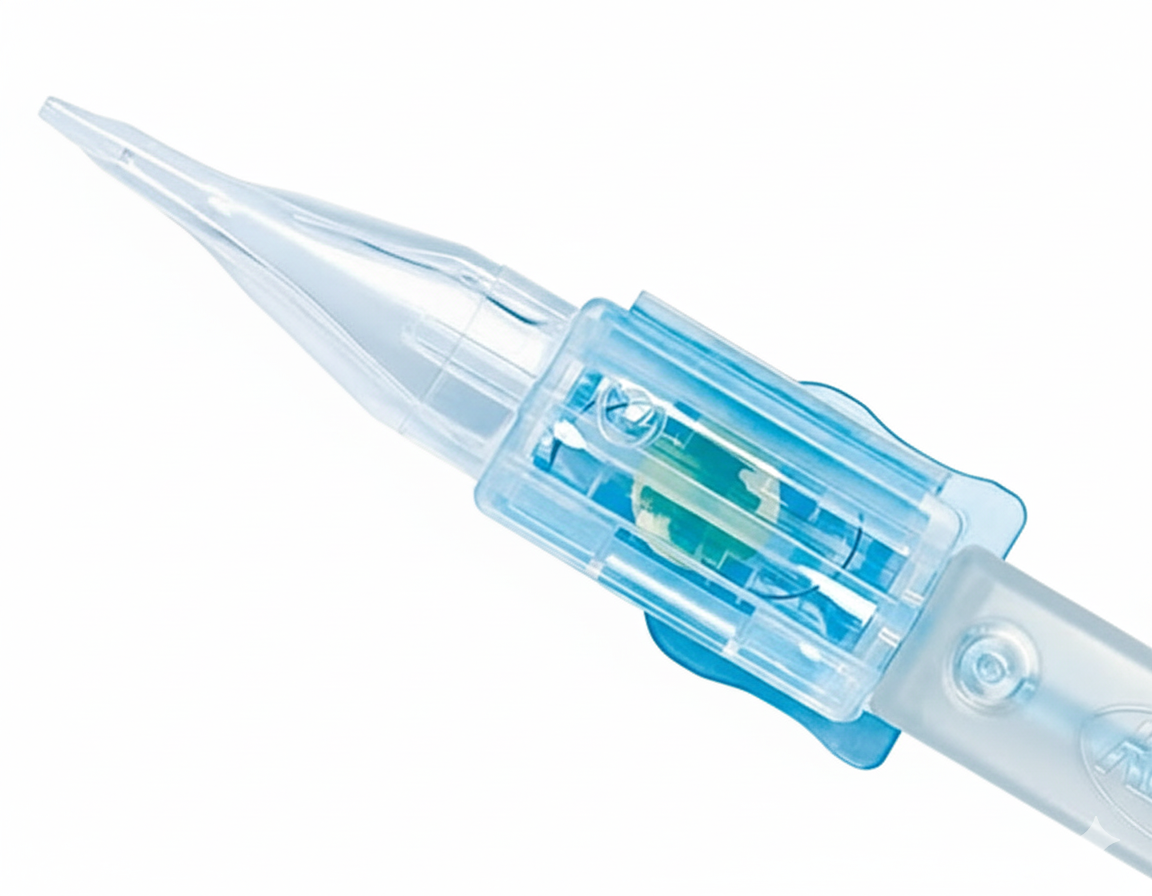

- Preloaded injector system ensures sterile and easy implantation.

- Low delivery force minimizes insertion risks.

- Suitable for small incision surgeries (2.4 mm).